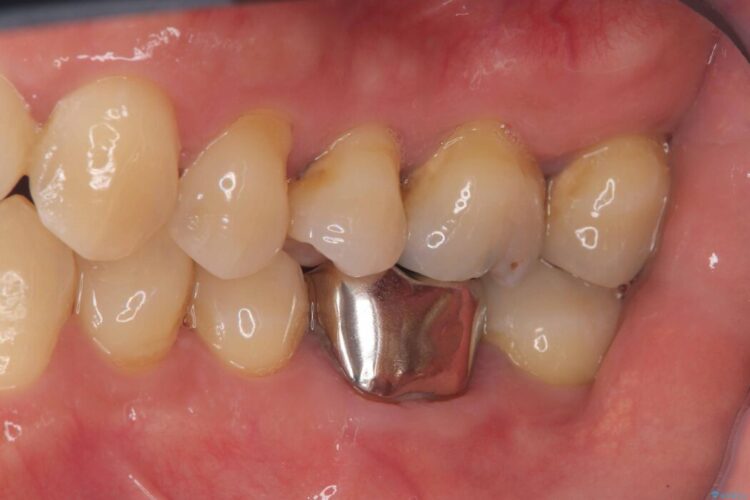

レントゲン検査にて、根尖および側枝付近に骨の透過像が認められました。

さらに精査したところ、根のパーフォレーション(根に穴が開いてしまっている状態)が確認されたため、

患者様と相談のうえ、インプラントにて治療を行うこととしました。